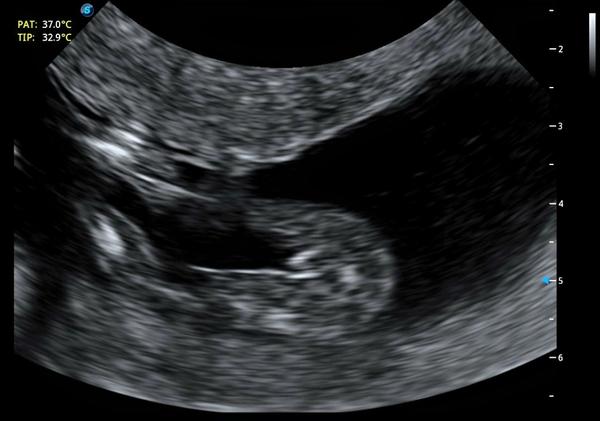

Poslala nám fotku z UTZ z 15. týdne grav., prý si máme doma udělat kvíz.

bohužel z jednoho snímku posuzovat pohlaví jednoduše nejde, je nutné vyšetření v reálném čase.